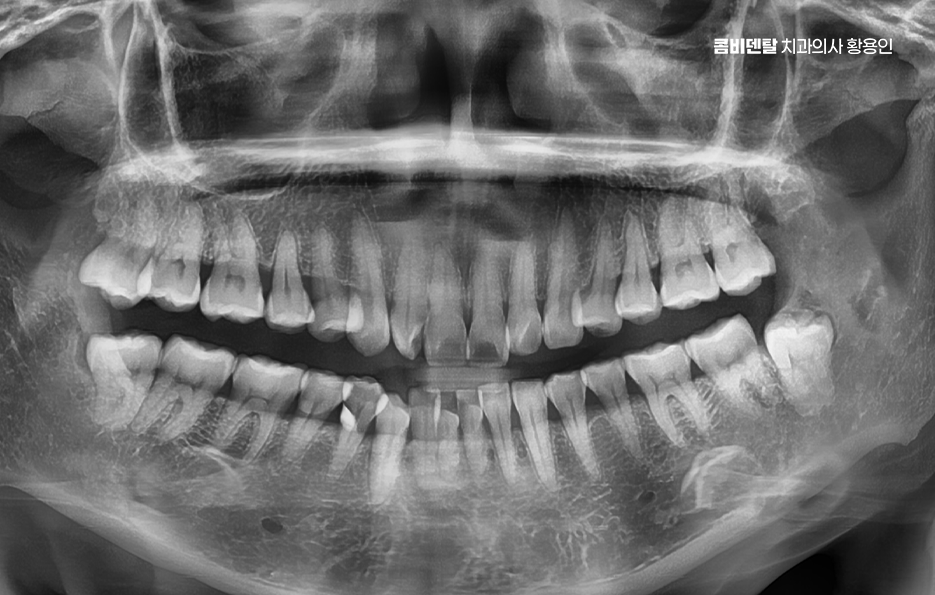

사랑니는 보통 10대 후반에서 20대 초반 사이에 나기 시작하는 어금니 맨 끝쪽의 치아로 사람마다 나는 시기도 다르고, 아예 나지 않는 경우도 있고, 똑바로 나지 않고 누워서 나거나 비스듬히 나는 경우도 있었어요.

특히 아래쪽 사랑니는 공간이 부족한 경우가 많아서 정상적으로 나기보다는 매복되거나 비뚤게 나는 경우가 많아서 문제가 생기기 쉽고, 결국 문제가 심해지다가 발치를 안하기 어려운 단계로 이어지는 경우가 많이 있어요

그 이유는 아래턱 뼈가 위턱보다 단단하고 밀도가 높아서 치아가 쉽게 안 빠지고, 하치조 신경도 가까이 있기 때문이고 매복된 사랑니일수록 치료가 까다로워질 수 있다는 점에서 사랑니 발치 경험이 많은 치과의사를 잘 만나는 것도 중요한 거예요

결론적으로 아래 사랑니 발치를 앞두고 있다면, 미리 대비하는 게 중요하며 발치 전날에는 과도한 음주는 피하고, 충분한 수면을 취하는 게 좋겠고 발치 당일에는 식사를 가볍게 하고, 시술 후에는 냉찜질을 꾸준히 해주는 게 부기 완화에 도움이 되며 특별한 증상이 없어도 정기적인 엑스레이 검사로 상태를 체크하고, 필요하다면 조기에 발치를 결정하는 게 좋은데 아래 사랑니 발치 통증은 누구에게나 부담이 되는 부분이긴 하지만 올바른 치료에 대한 이해와 접근을 통해 누구나 느낄 수 있는 통증을 좀더 줄이고 지혜롭게 해결하시길 바라고 있어요